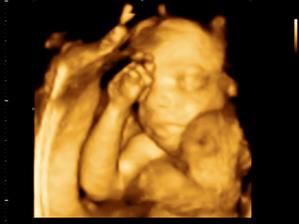

30.03. - (20+5), tak na dnešní kontrole dopadlo všechno na 1*, vážíme už 380g a z našeho Marečka se nakonec vyklubala Amálka, která měla mezi nožičkama zamotenej pupečník 😀 Pan doktor říkal, že tentokrát, je to opravdu na 100%

27.04. - (24+5) video, tak z videa nakonec sešlo. Dohodli jsme se s panem doktorem, že se mu ozvu, tak za 14 dní, až Karolínka ještě povyroste. Teď má v bříšku ještě moc místa a nebylo by to úplně ono. Tak jsme alespoň dostali několik foteček a dva doktoři nám potvrdili, že jde skutečně o holčičku.

11.05. - (26+5) dnes jedeme na video

video se povedlo, máme asi 6 cca 5 - 10ti vteřinových videíí.Bylo to super. Karolínka se zase mlela jako drak. Je taková živoučká 😀